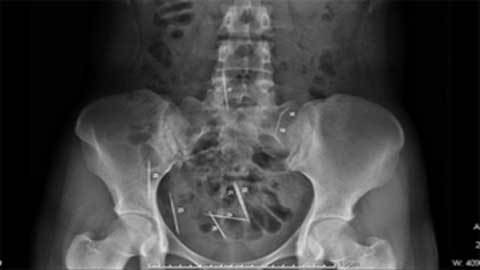

Bệnh viện đa khoa Phúc Châu (Phúc Kiến, Trung Quốc) cho biết, vừa phẫu thuật lấy thành công lấy 3 cây kim từ ổ bụng, gan và thận cho một cậu bé 5 tuổi.

Trước đó, Tiểu Diệp bị tai nạn bị thương ở bụng, lưng và đầu, sau đó được đưa

vào viện cấp cứu. Các bác sĩ đã tiến hành chụp phim và phát hiện trong bụng, gan

và thận của Diệp có 3 dị vật chỉ dài và nhỏ như chiếc kim khâu. Ngay sau đó,

Tiểu Diệp tiếp tục được các bác sĩ nhi khoa thăm khám và làm các biện pháp chiếu

chụp kỹ hơn đã phát hiện ra ba dị vật đó chính là 3 cây kim.

Trong số 3 cây kim này thì một cây đã có dấu hiệu bị gỉ và 2 cây còn lại quay

ngược lên chứ không đâm vào cơ thể. Đây là ca mổ tương đối khó vì ba cây kim rất

nhỏ, có dấu hiệu bị gỉ, chỉ cần một sơ suất nhỏ có thể nguy hiểm đến tính mạng

của Tiểu Diệp.

| Cây kim trong bụng |